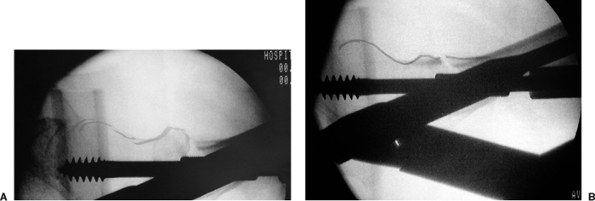

guide pin is inserted centrally and very deep using both the AP and

lateral x-rays for guidance (Fig. 17.15A,B).

The guide pin placement should then be confirmed to have the optimal

tip-apex distance (TAD) of 5 to 10 mm from the articular surface of the

femoral head (see Fig. 17.15C).

Figure 17.15. A. Appropriate guide pin placement on the AP x-ray. B. Appropriate guide pin placement on the lateral x-ray. C. The technique to measure TAD.

|